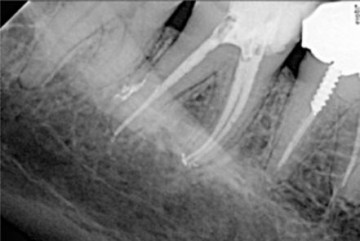

Postoperative x-ray after shaping with 2Shape, apical finishing using F40 and obturation with pure thermomechanical condensation technique thanks to Revo Condensor.